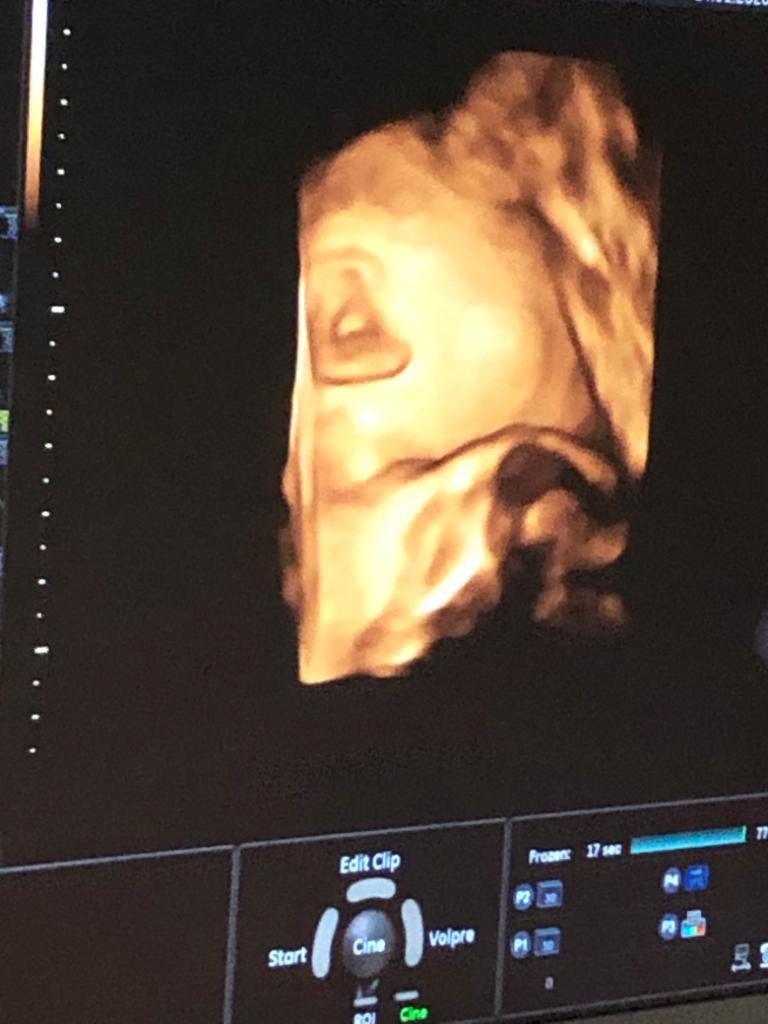

Wczoraj byłam na Usg (28+6) Młode ustawione już głowa w dol. Co ciekawe tak ustawione że to co " najważniejsze" pokrywane🙂

Buzia schowana w moje biodro.... Próbowaliśmy chyba wszystkiego i jedynie co pokazało to ucho 🙈

Płeć niewidoczna, bo zasłonięte piętą 😂

A do tego odwrócone jest brzuszkiem w kierunku mojego kręgosłupa więc nawet ciężko rączki czy nóżki było zobaczyć (nam amatorom zdjęcia usg)

... Mój partner wyszedl z gabinetu z mina obrażonego dziecka 😂😌🙈😎😀😂

Waga około 1300